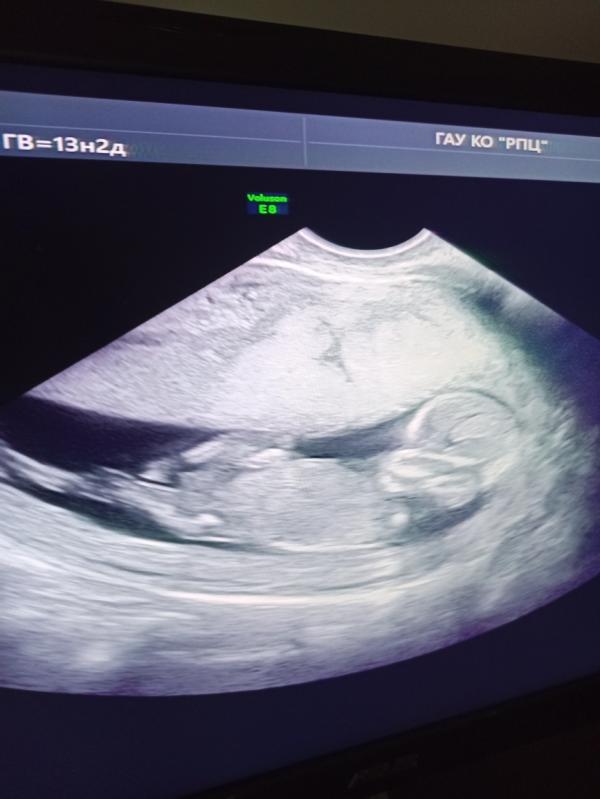

Вот и прошли мы первый скрининг

С малышом всё хорошо по узи,развивается по нормам срока 💞

Дождемся ещё результаты крови и точно убду спокойна.